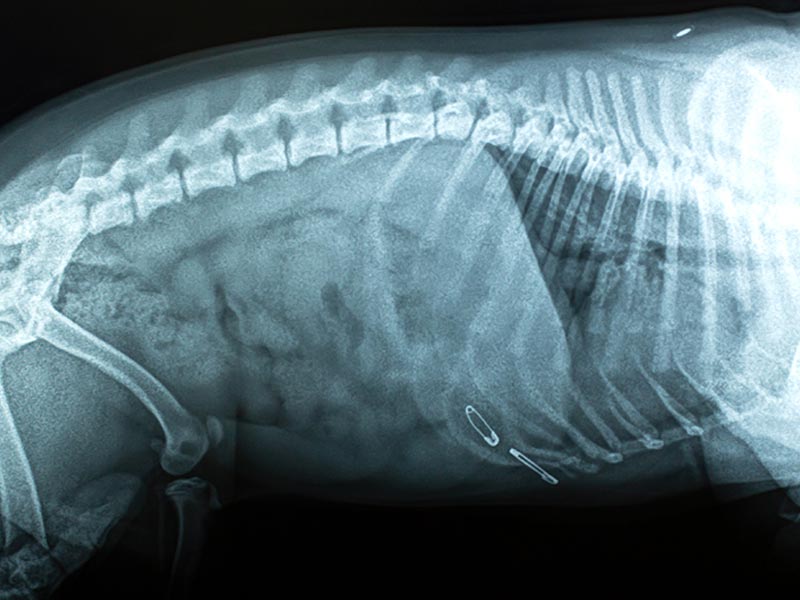

We are proud to be on the cutting edge of medical technology. Radiology is a technique and diagnostic tool we use to look inside the body in an entirely non-invasive way. X-rays allow us to create images of all the body’s organs. In other words, the use of radiology gives us a view of the internal organs in your pet’s body that we otherwise could not see. It’s a valuable diagnostic tool that helps veterinarians detect and prevent illnesses.

The images produced by digital radiography are of much better quality than film radiographs and can be manipulated digitally, giving us the best possible radiographic information to help us diagnose your pets.